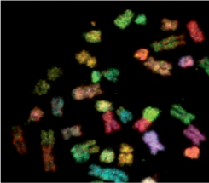

- Chromosome analysis.